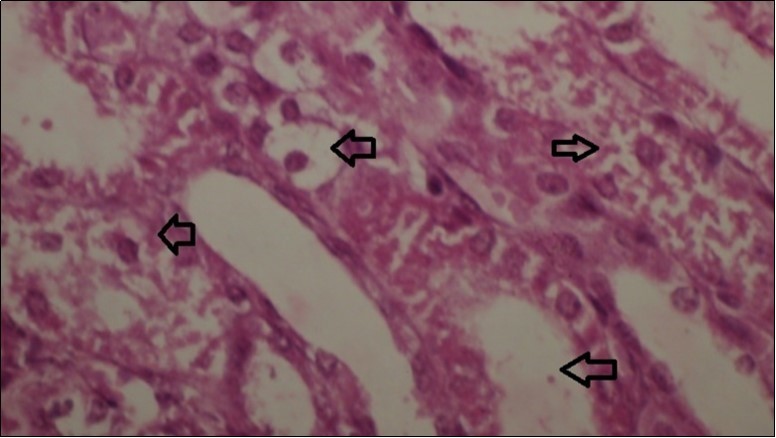

Figures 7.kidneys (dead cattle less than 1 year old) showed severe hydropic degeneration of renal tubular epithelium accompanied by dilated renal tubules, vesicles formations and casts (arrows). (H&E, X 60)

kidneys (dead cattle less than 1 year old) showed severe hydropic degeneration of renal tubular epithelium accompanied by dilated renal tubules, vesicles formations and casts (arrows). (H&E, X 60)